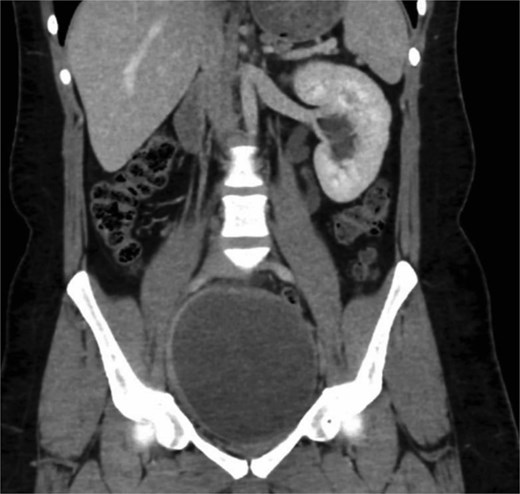

Computed tomography (CT) of the pelvis demonstrated a large right seminal vesicle cyst measuring 8.2 × 6.4 × 5.1 cm, left-sided moderate hydroureteronephrosis, and absence of right renal or ureteral structures (renal agenesis). The left kidney has compensatory hypertrophy, and no other significant abdominal or pelvic abnormalities were noted (Fig. 1).

Coronal CT scan showing an enlarged right seminal vesicle cyst measuring 8.2 × 6.4 × 5.1 cm and ipsilateral renal agenesis.